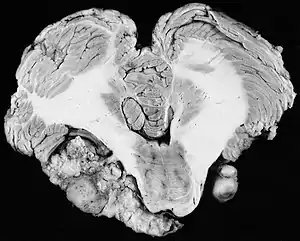

![]() | |

| Bilateral schwannomas in a patient with neurofibromatosis 2 | |